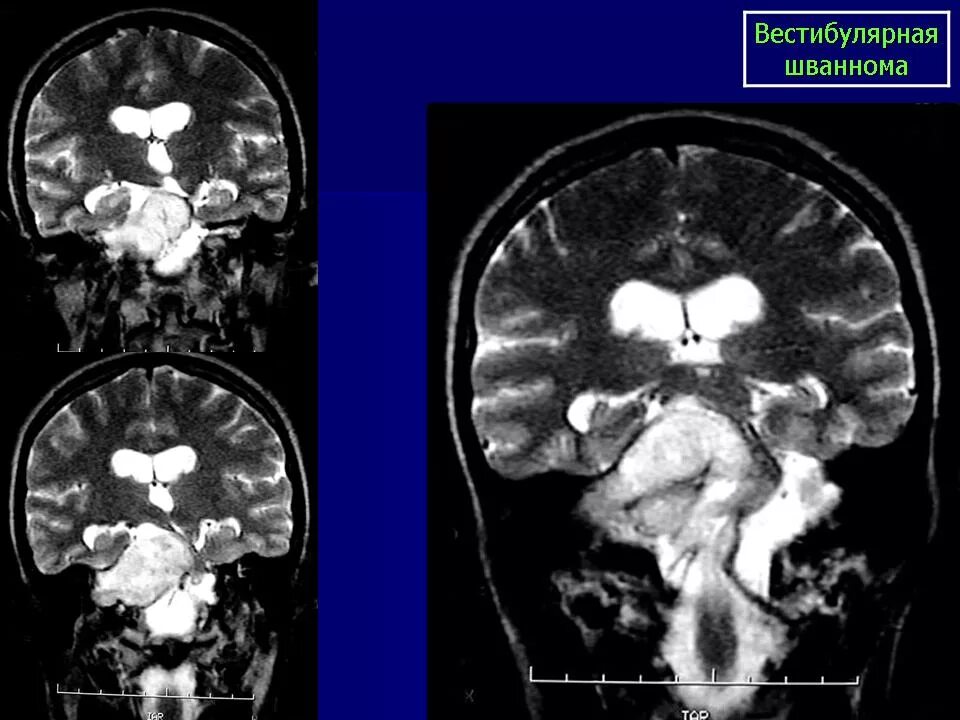

Мрт головного мозга мосто мозжечкового угла